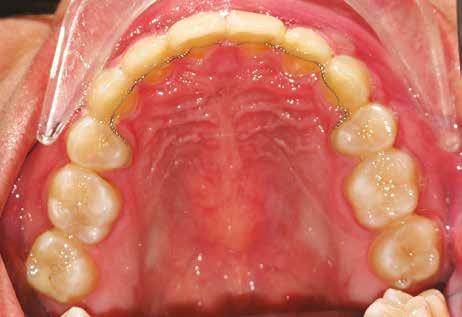

A 10 éves férfi páciens a felső frontfogai késői/nem megvalósuló előtörése miatt kereste fel a rendelőnket. A klinikai és a radiológiai vizsgálat során a jobb felső nagymetszőfog impakcióját észleltük (1. ábra). A fog horizontális tengelyállással és dilacerált gyökérrel rendelkezett. A felső dentális középvonal a fogak vándorlása miatt jelentős mértékben elcsúszott. A bal felső kismetszőfog is rendkívül kedvezőtlen pozícióba került.

Dr. Kazem Dalaie, dr. Samin Ghaffari, dr. Mazir Mir (Irán, Németország) 1. a ábra: Az intraorális felvételen jól látható a jobb felső nagymetszőfog lehetséges impakciójára utaló foghiány.

1. b ábra: A panoráma röntgenfelvételen megfigyelhető a teljes impakcióban lévő jobb felső nagymetszőfog. 1. c ábra: A CBCT felvétel is igazolja a jobb felső nagymetszőfog impakcióját.